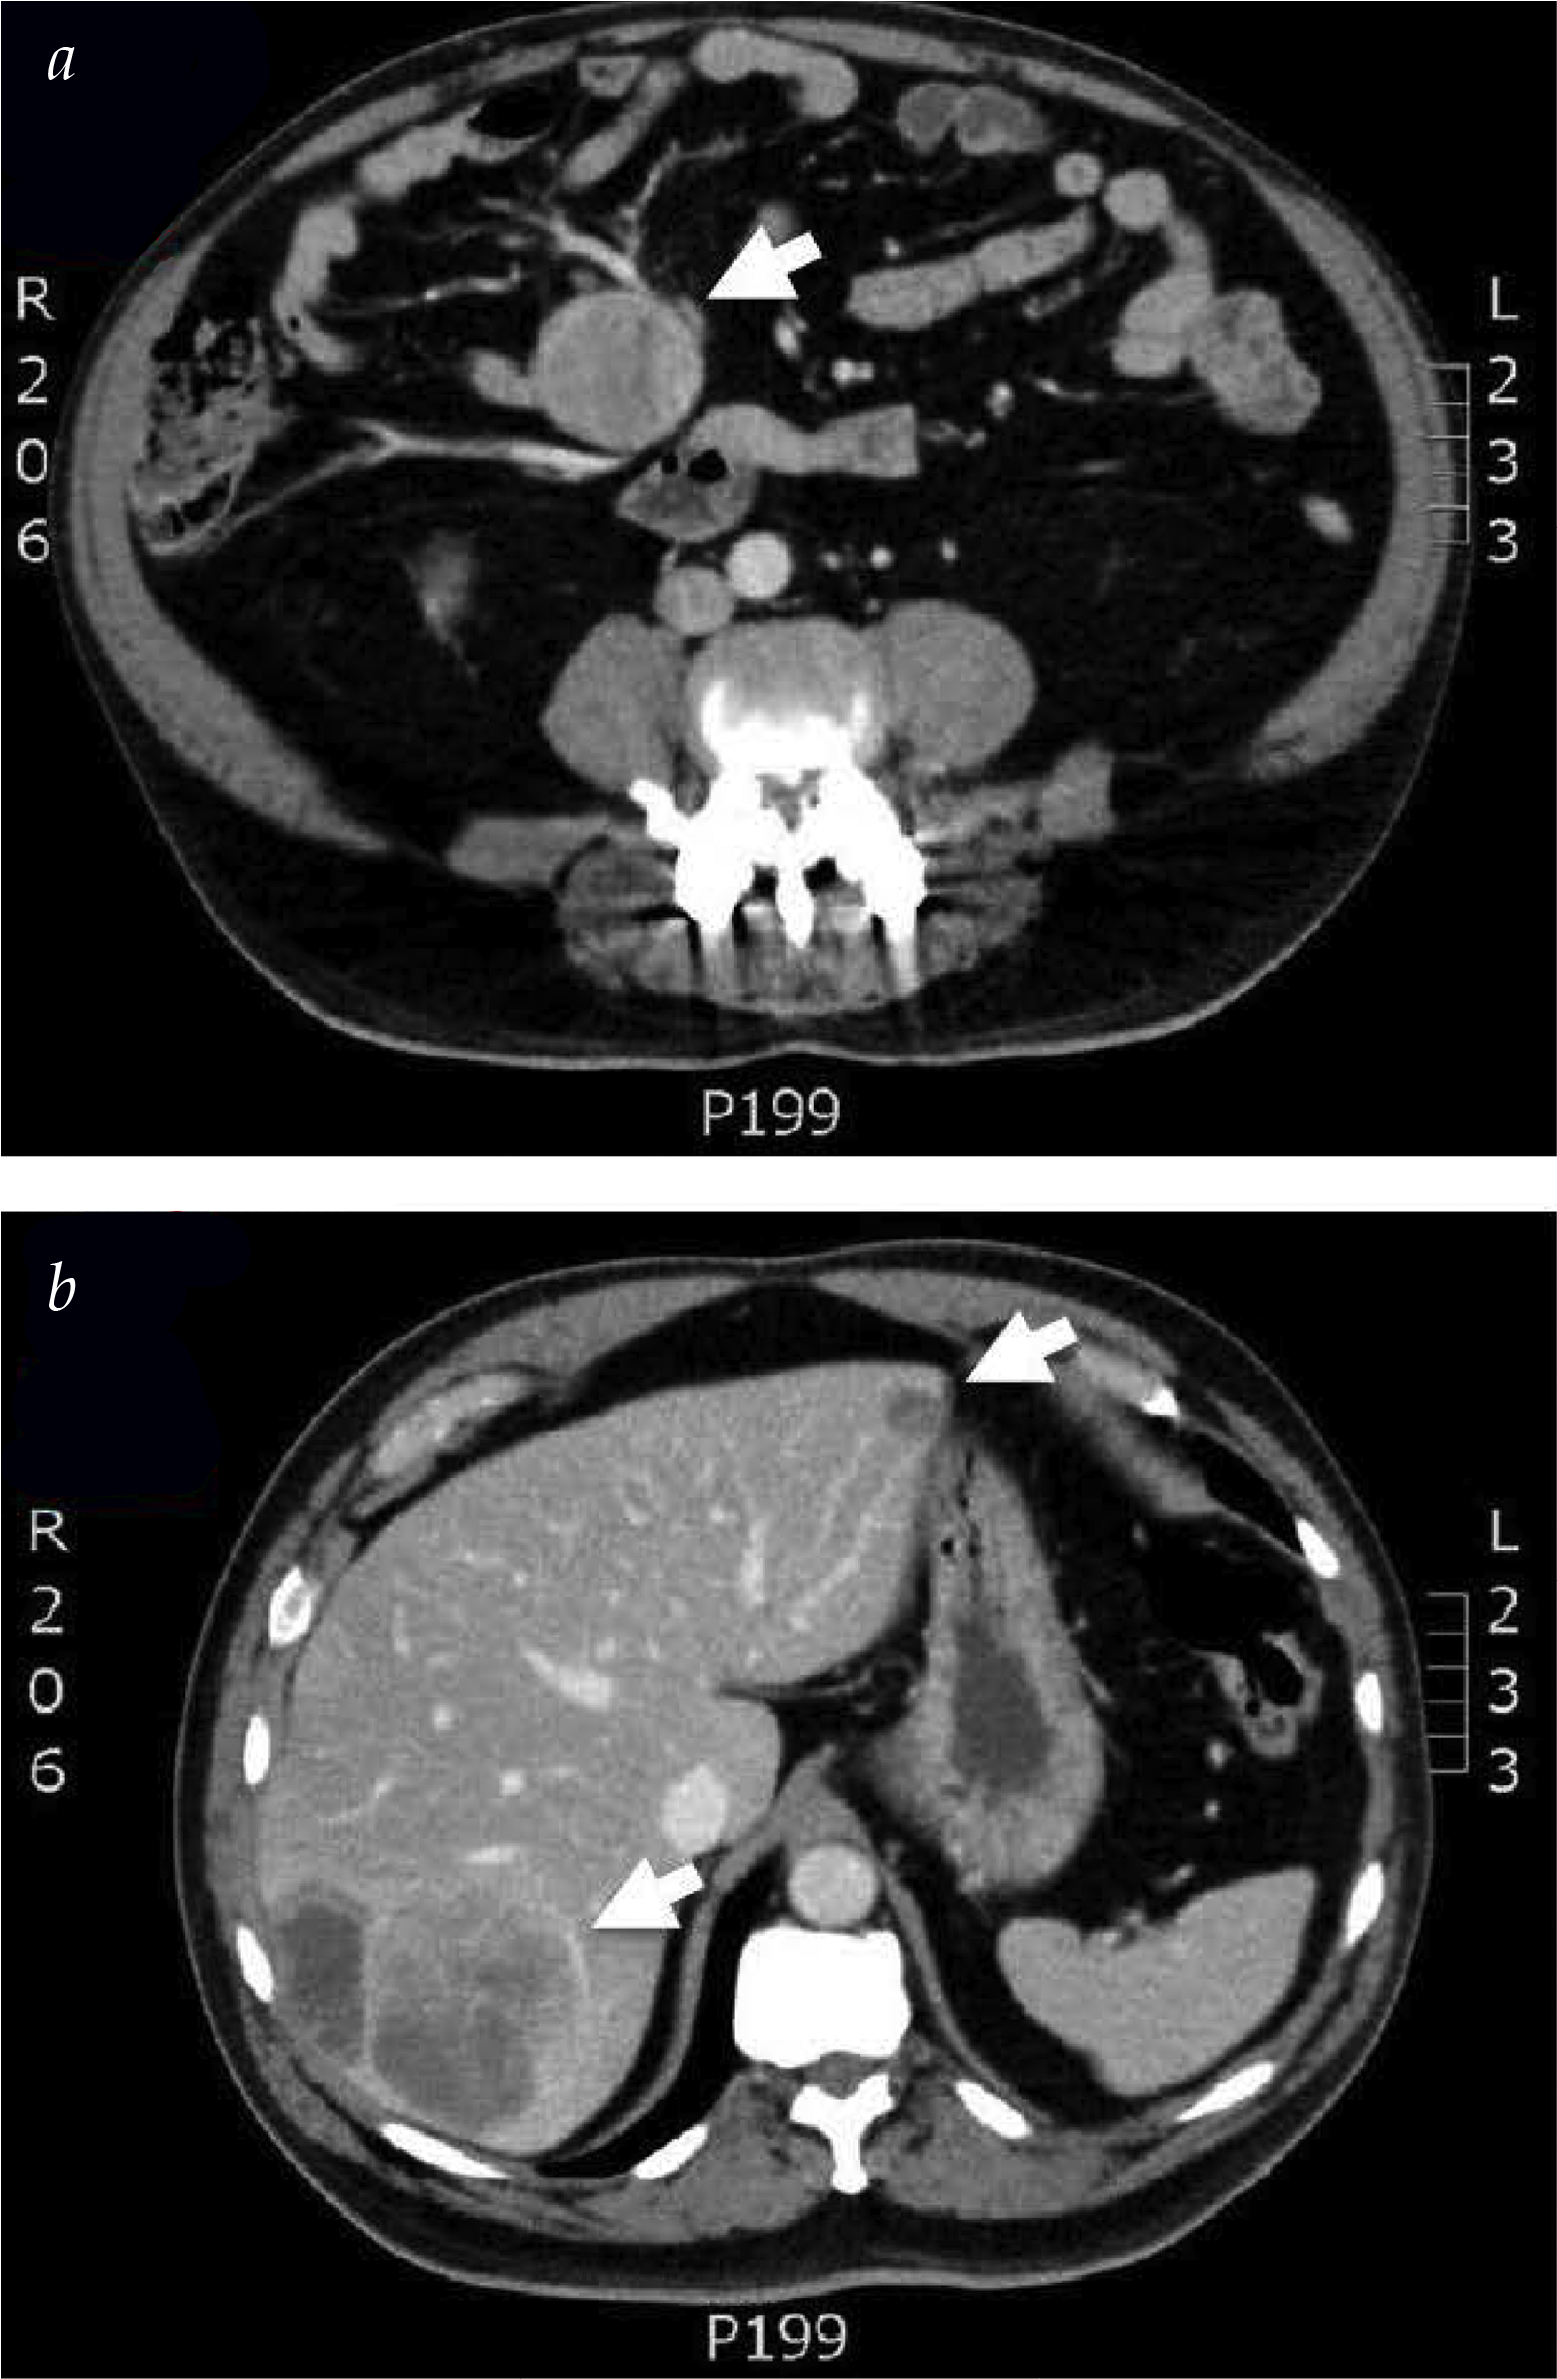

CT

- Small bowel carcinoid tumors:

- Are often small (less than 2 cm median size):

- And are thus difficult to identify by cross-sectional imaging

- Given the hypervascularity of these tumors:

- Arterial phase:

- May improve visibility

- More commonly:

- CT imaging reveals:

- Mesenteric or hepatic metastases:

- Without a small bowel mass

- The classic CT appearance demonstrates:

- A “spokes in a wheel” pattern:

- With a mesenteric nodal mass (wheel)

- With radiating desmoplastic fibrosis

- The occult primary small bowel carcinoid tumor:

- Is often in the bowel adjacent to the nodal metastases:

- And may manifest with radiographic signs of:

- A partial small bowel obstruction